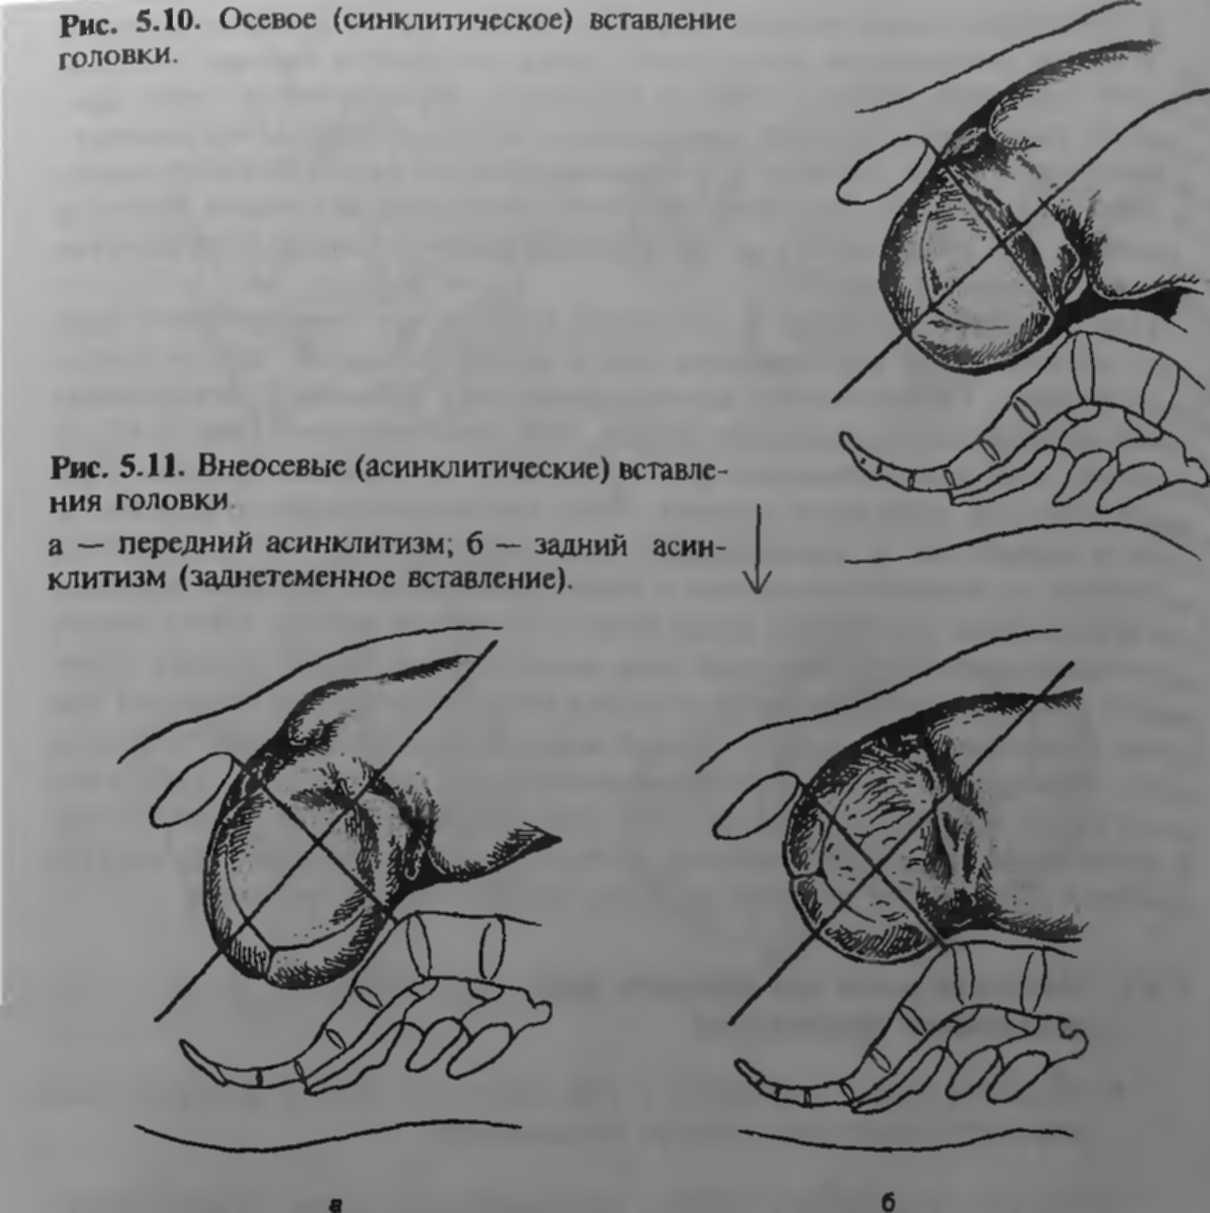

Стрелоаидный шов вправом косом размере

Передний асинклитизм биомеханизм родов